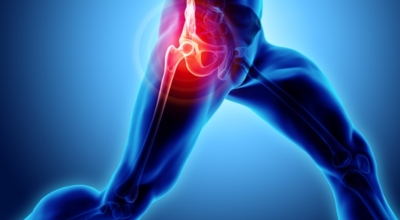

각별히 젊은 남성에게 잘 발생하며 엉덩이와 골반 주위에 뻐근한 통증이 동반되며 정상적인 보행이 되지 않고 절뚝거리는 증상이 나타난다면 대퇴골두 무혈성 괴사일 가능성이 있답니다. 이 증상은 괴사 부위의 골절이 발생되어 고관절 손상으로 이어지면 발생하는 증상으로 아직까지 정확한 원인은 규명하기 힘드나 과음이나 고지혈증, 스테로이드 과남용이 영향을 줄 수 있어요.

3. 고관절 통증 증상 - 엉덩이 통증